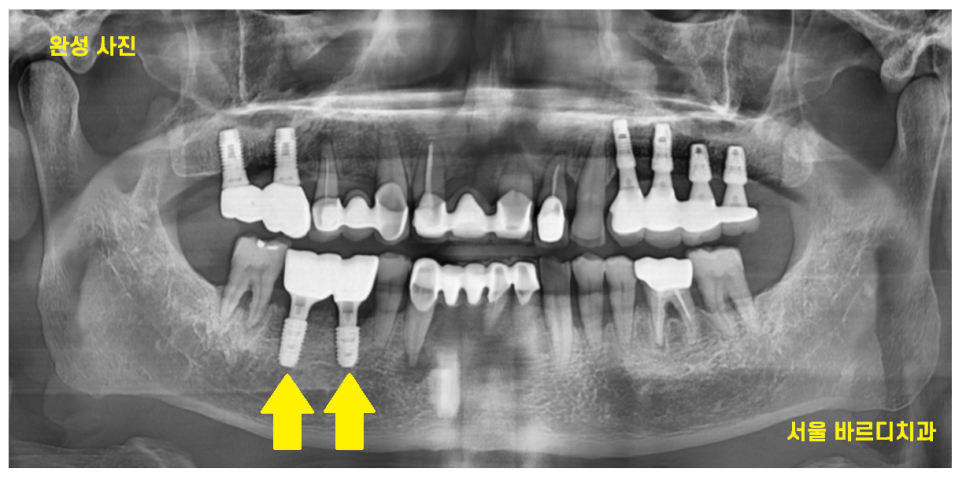

치료 후 잇몸 염증이 많이 사라지긴 했지만

한번 내려간 잇몸의 경우

회복이 어렵습니다.

정기적으로 하남시청치과에 방문하셔서

임플란트와 잇몸

두가지 모두 관리하시기로 약속하셨답니다~